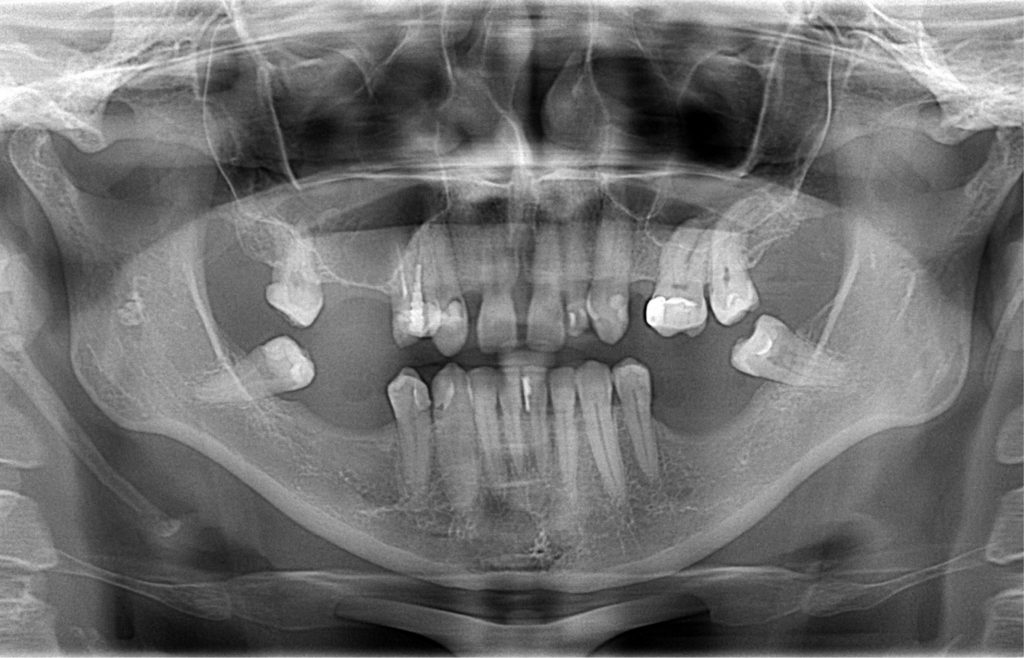

STRESZCZENIE: Z zespołem Eagle’a możemy się spotkać w codziennej praktyce stomatologicznej. Przy wykonywaniu zdjęć pantomograficznych powinniśmy zwracać uwagę na długość wyrostków rylcowatych badanego pacjenta. Jeżeli długość któregoś z wyrostków jest większa niż 30 mm i dodatkowo występują silne, często nietypowe, jednostronne dolegliwości bólowe, to powinniśmy skierować pacjenta na konsultację laryngologiczną, by potwierdzić lub wykluczyć zespół Eagle’a.

SUMMARY: We can come across a patient with Eagle syndrome in everyday dental practice. When taking a pantomographic x-ray image, we should always pay attention to the length of the patient’s styloid processes. If the length of any of the processes is greater than 30 mm and additionally the patient suffers from severe, often unusual, unilateral pain, then our concern should be increased. In this case, an ENT consultation may be necessary in order to confirm or rule out Eagle syndrome.